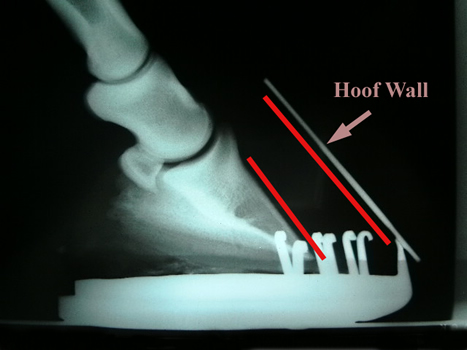

The hoof grows from two separate areas. The base of the foot generates the sole and the coronary band generates the hoof wall which grows continuously downwards. The ‘white line’ is the join between these two parts of the hoof. In normal circumstances most of the weight of the horse is supported by the part of the hoof wall contacting the ground. In effect, the horse ‘hangs’ off the inside of the hoof wall rather than standing on the sole. The structures attaching the hoof wall to the bone column of the horse are called the laminae. Laminitis is inflammation of these laminae. To give you some idea of the pain levels involved in laminitis; imagine your fingernail is a hoof (which in affect it is). Imagine your fingernail solidly whacked with a heavy hammer so that there is bleeding and pressure under the nail. That hurts. Now imagine having to do a handstand with a significant amount of your bodyweight resting on that fingernail. In severe laminitis, the horse is standing on 4 ‘whacked’ fingernails. Above is an an X-ray of a mild laminitis. Note the shoe has been left on for now. A metal strip has been fixed to the hoof wall to show its position. See how there is a slight divergence between the two red lines – some rotation of the bone has occurred.